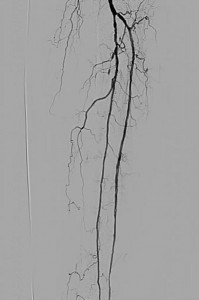

Angiography revealed bilateral occlusions of the anterior and posterior tibial arteries. Iliac and femoral arteries were free of significant disease (Figure 1):